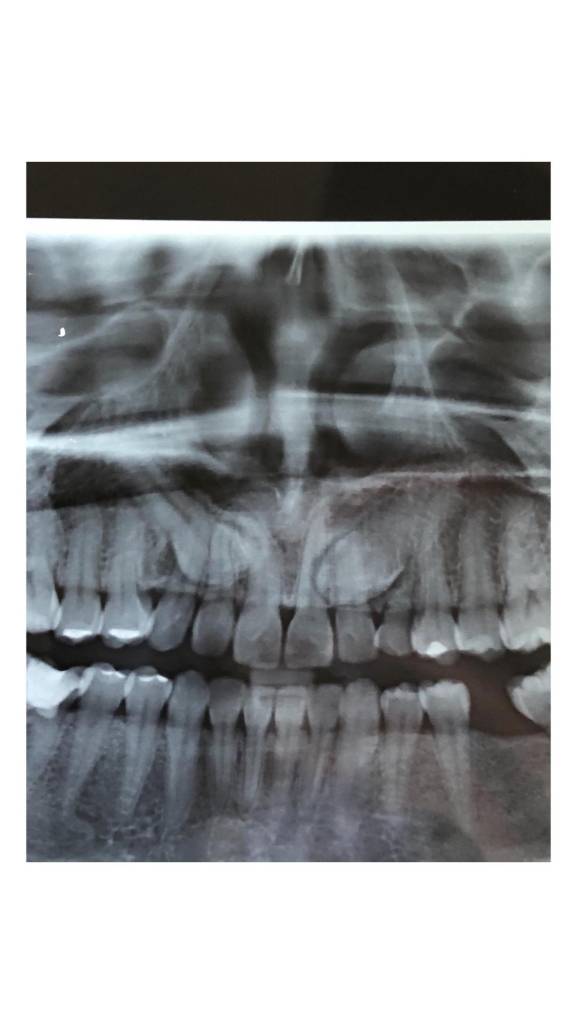

Cada cirugía comienza con un diagnóstico detallado mediante estudios radiográficos y, cuando es necesario, tomografías digitales que nos permiten planificar el procedimiento con exactitud. Esto no solo optimiza los resultados, sino que también reduce la posibilidad de complicaciones y mejora el postoperatorio.